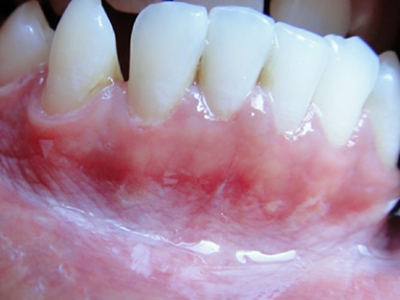

牙龈

白斑

口腔毛状黏膜白斑牙龈白斑图

口腔毛状黏膜白斑患者的牙龈出现白斑,皮损表现为点圈状的不规则小面积分布,直径1mm左右,患者无明显自觉症状,需及时治疗,避免扩散。